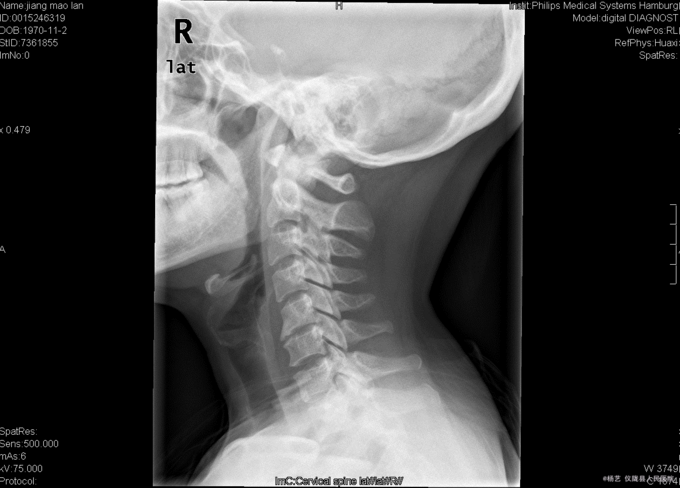

患者蒋茂兰,女,45岁0月,因“头晕伴视物旋转10+月,加重1+月。”入院 10+月前患者无明显诱因出现头晕、头昏;视物旋转,偶伴有呕吐,呕吐为胃内容物;间断发作,发作时持续时间不等,休息后明显缓解。无活动障碍;无肢体麻木、乏力;无行走不稳;无发热、头痛等,1+月前患者上述症状加重,患者于当地医院就诊,治疗未见明显好转。颈椎MRI示:颈5/6椎间盘突出。现患者为求进一步诊治就诊于我院,门诊以“C5/6椎间盘突出症伴脊髓神经不全损害”收入我科。

查体:T:36.9oC,P:78次/分,R:19次/分,BP:109/72mmHg。神志清楚,无病容,皮肤巩膜无黄染,全身浅表淋巴结未见肿大。。颈静脉正常。心界正常,心律齐,各瓣膜区未闻及杂音。胸廓未见异常,双肺叩诊呈清音,双肺呼吸音清,未闻及干湿啰音及胸膜摩擦音。腹部外形正常,全腹柔软,无压痛及反跳痛,腹部未触及包块,肝脏肋下未触及,脾脏肋下未触及,双肾未触及。双下肢无水肿。 专科查体:视:脊柱外观无畸形,活动无异常,无皮肤破溃及窦道形成。触:椎体棘上、椎旁肌无压痛、叩痛,四肢感觉无明显减退,远端血运未见异常。动量:颈部屈伸、左右侧偏活动无明显受限,双上肢耸肩、屈伸肘关节、屈伸腕肌力5级,双手握力5级,双下肢伸髋、屈髋、外展、内收、伸膝、屈膝肌力5级,双足趾背伸肌力5级。双侧肱二、三头肌肌腱反射、膝腱反射、跟腱反射正常引出。双侧Hoffmann氏征阳性,Babinski征阴性,踝阵挛阴性,髌阵挛阴性。 辅助检查:外院MRI示:颈椎退行性变,颈5/6椎间盘突出。垂体区:空泡蝶鞍?

综上初步诊断:1、颈5-6椎间盘突出症伴脊髓神经不全损害;2、白癜风 经前路颈5/6椎间盘切除、椎管及椎间孔减压、椎间融合器植骨融合内固定术。 手术发现:  颈5/6椎间隙变窄,椎间盘髓核干涩,无光泽。颈5/6椎间隙后份少量骨赘生成,椎间盘向后方突出,压迫硬脊膜。术中夹出数块突入椎管内的椎间盘髓核组织及增生骨赘。充分减压后,可见硬脊膜恢复膨隆,双侧神经根松弛,术中未见脑脊液漏。